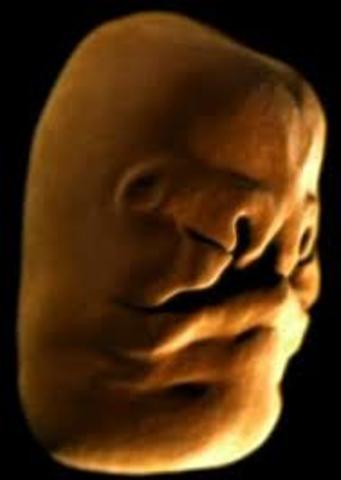

• Day 35

Day 35

Face plates forming

• Day 36

Day 36

Cleft palate may occur